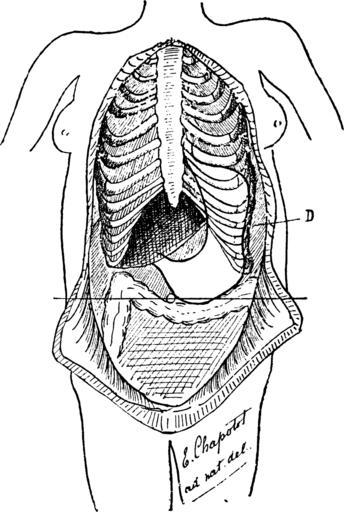

| Keywords: EstomacCorset page068.png Figure 18 d'après nature ESTOMAC VERTICAL AVEC BILOCULATION D Déformation thorax correspondant au rétrécissement de l'estomac On voit les côtes déformées faisant un angle en avant de la ligne axillaire; ellers sont très-inclinées en bas http //fr wikisource org/wiki/L E2 80 99Estomac_et_le_Corset L'Estomac et le Corset page 69 1892 Le dr Eugène Chapotot L'Estomac et le Corset PD-Art Corsets and health Diagrams of the human stomach Language-neutral diagrams | ||||